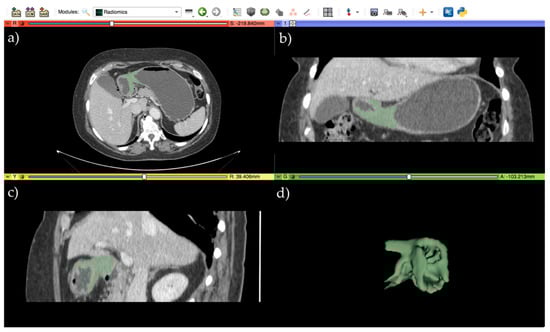

2.3. Image Segmentation Analysis